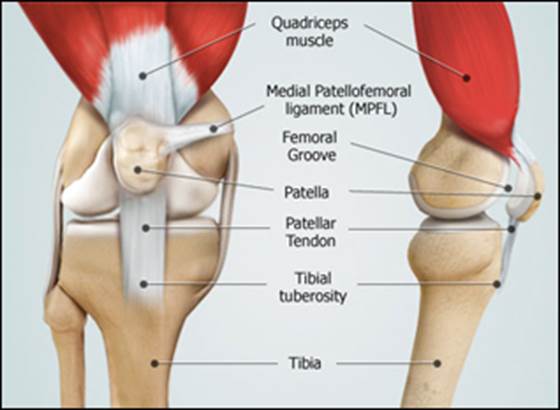

Apex patellae

Apex patellae 117 фото